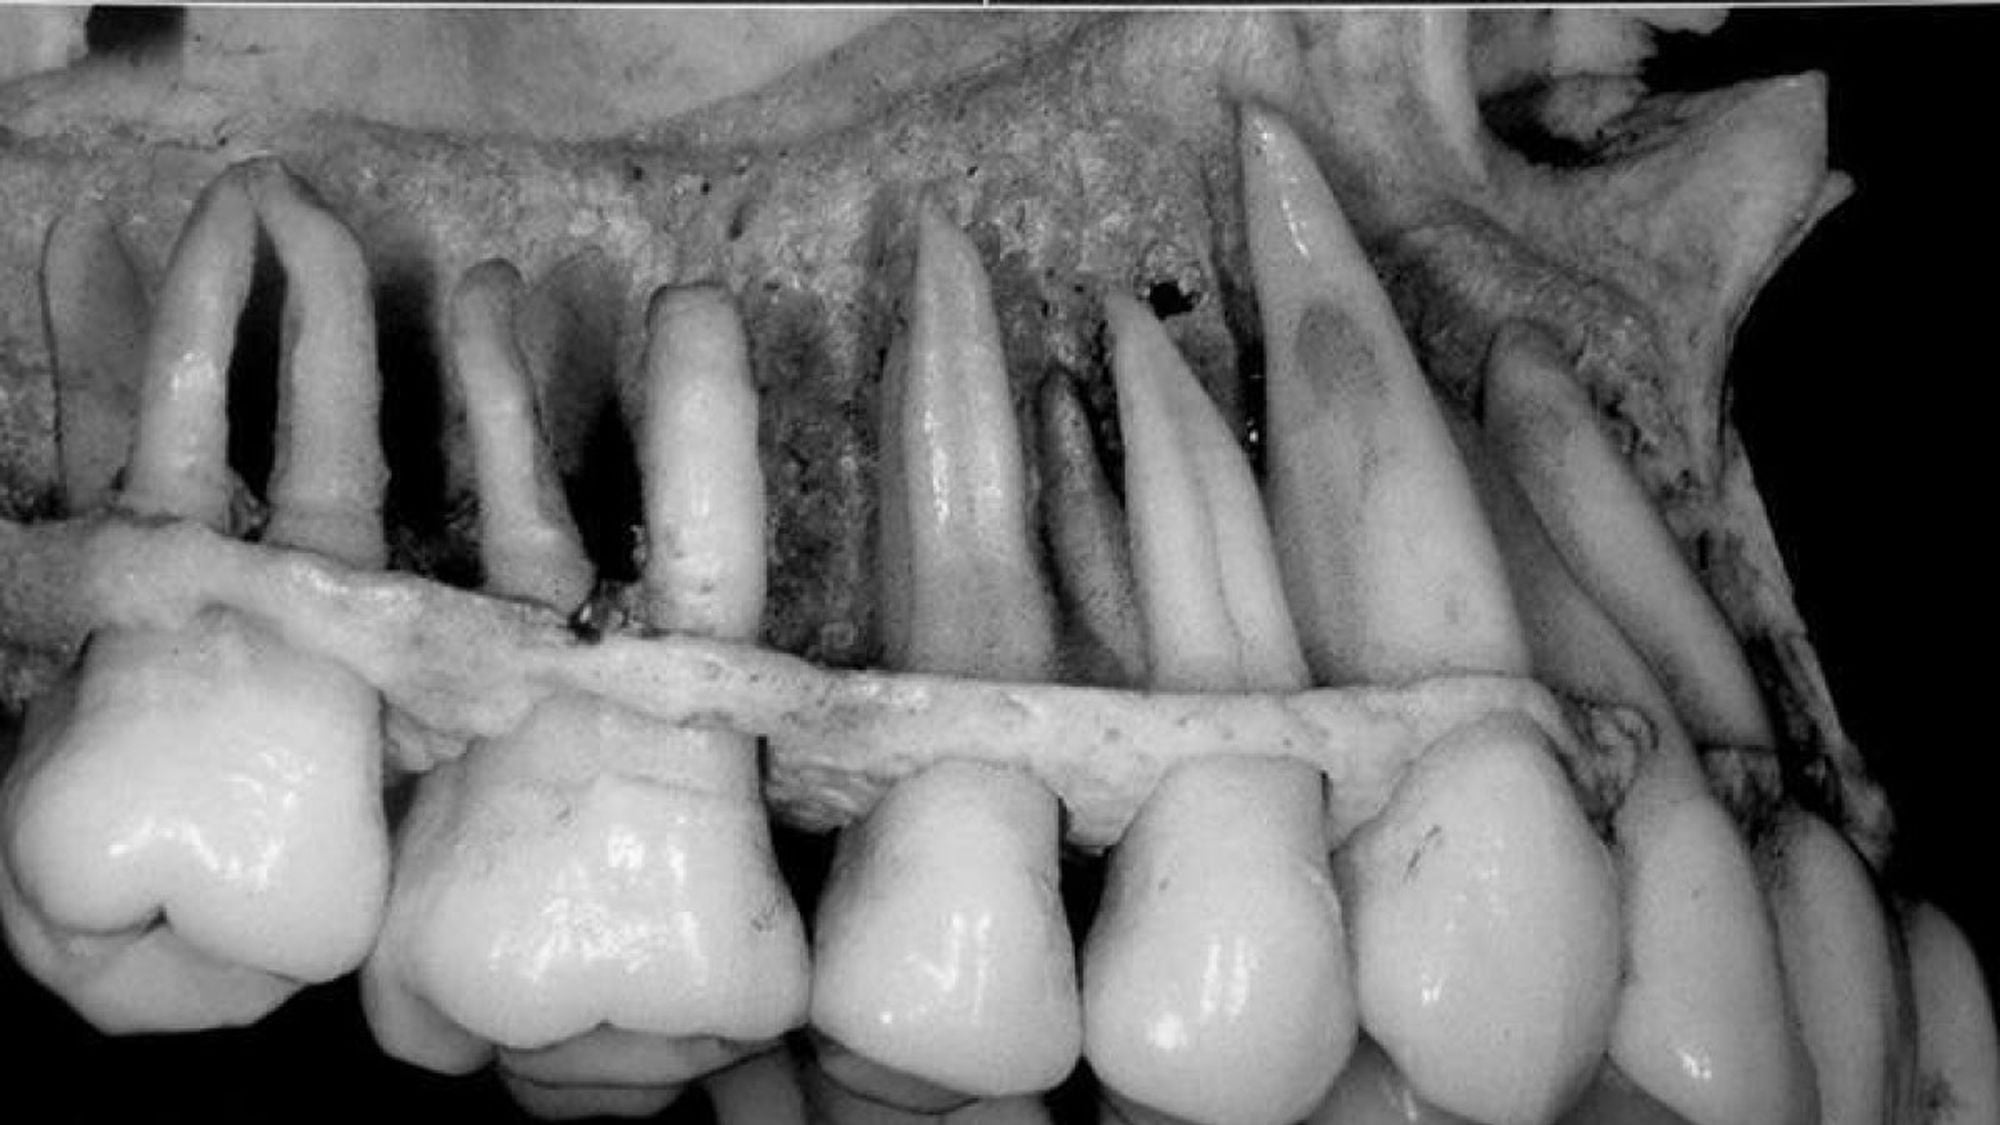

- Dişlerinizin 3'te 2'si diş etinizin altında konumlanır.